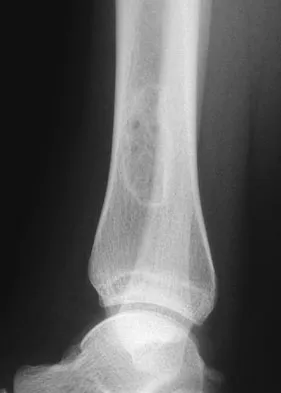

A previously asymptomatic 14-year-old girl sustained a twisting injury to her ankle. Radiographs are shown in Figures 2a and 2b. Management should consist of

Explanation

The radiographs show a well-defined, irregular, eccentric lesion in the distal tibia metaphysis with a thin sclerotic margin. The radiographs are diagnostic of nonossifying fibroma, a common entity in this age group and in this location. No further work-up is indicated. The patient was asymptomatic prior to the injury and the lesion is small and thus not worrisome for an impending pathologic fracture; therefore, no treatment is indicated beyond observation. The natural history of these lesions is to gradually ossify as the patient reaches skeletal maturity. Menendez LR (ed): Orthopaedic Knowledge Update: Musculoskeletal Tumors. Rosemont, IL, American Academy of Orthopaedic Surgeons, 2002, pp 69-75.